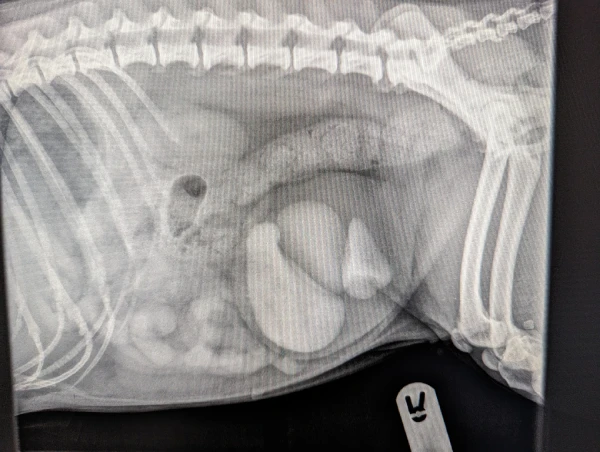

X-Ray of urinary stones in Willow

Unfortunately for Willow, the urinary stones had grown to such a size that surgery was the only option to remove them as they were too big for dissolution or urohydropulsion, which don’t involve an operation.

Elaine Stewart, the lead vet who carried out the operation along with veterinary surgeon Julia White, said: “A heart shaped urinary stone was one in a number of stones we removed from Willow. The challenge of the surgery was removing such large stones through the bladder while minimising any tissue damage.